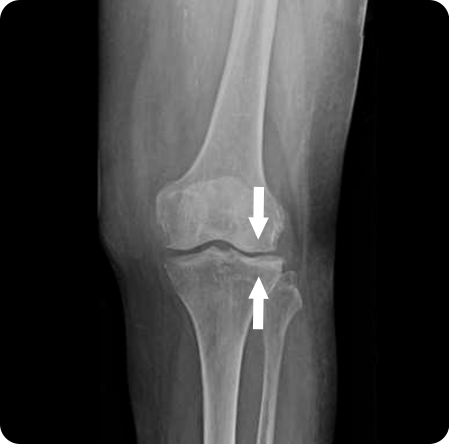

퇴행성관절염으로 연골이 마모되고 관절이 내려앉게 되어

진행된 휜 다리(O 다리, X 다리)를 바르게 교정하여

무릎 내 외측에 집중되어 있는 무게 중심을

고르게 분산시켜 관절염의 진행을 막는 수술법

입니다.

무게 중심이 내측으로

쏠려 있는 O다리 수술

경골을 절골하여 원하는 각도로 벌려 무게 중심이

바깥쪽으로 옮겨지도록 교정

합니다. 절골한 부위를

금속판과 나사로 고정해 뼈가 안정적으로 붙도록 합니다.